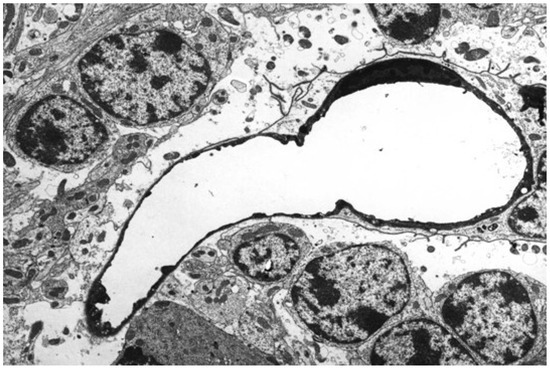

- Morgan, K.T.; Kelly, B.G. Ultrastructural study of brain lesions produced in mice by the administration of Clostridium welchii type D toxin. J. Comp. Pathol. 1974, 84, 181–191. [Google Scholar] [CrossRef]

- Finnie, J.W. Ultrastructural changes in the brain of mice given Clostridium perfringens type D epsilon toxin. J. Comp. Pathol. 1984, 94, 445–452. [Google Scholar] [CrossRef]

- Gardner, D.E. Pathology of Clostridium welchii type D enterotoxemia. II. Structural and ultrastructural alterations in tissue of lambs and mice. J. Comp. Pathol. 1973, 83, 509–524. [Google Scholar] [CrossRef]